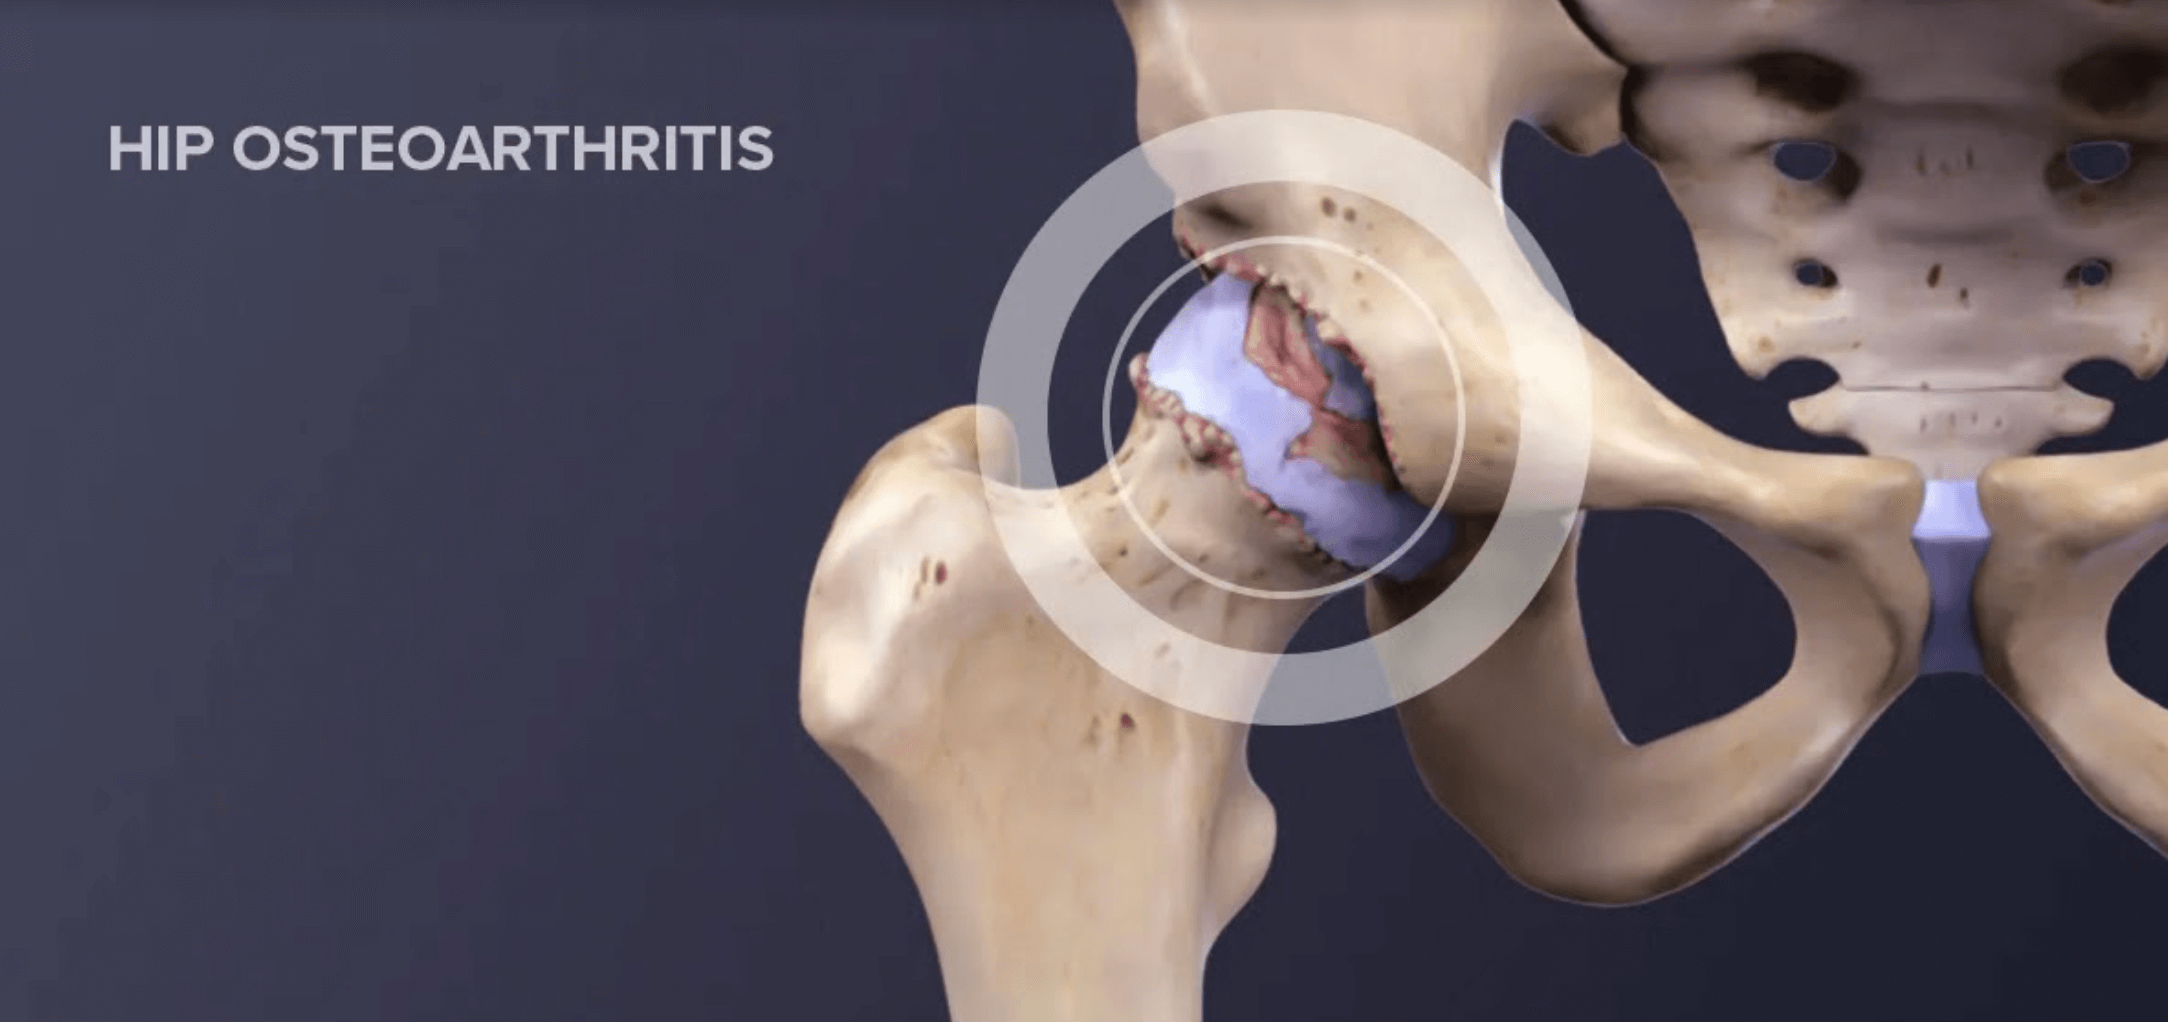

Arthritis is a term for inflammation of the joints and surrounding structures. There are many different types, the most common being osteoarthritis and rheumatoid arthritis, but arthritis also includes puerperosis and fibromyalgia (1). Osteoarthritis (OA) of the hip is a very common problem in Western society. It affects up to 25% of the population over 55 years of age, is more common in women, and genetic and lifestyle factors contribute to its onset, in addition to ageing. (10).

OA is a progressive wear and tear of the cartilage, resulting in bone-on-bone contact, which causes changes in the bone system. Of course, changes in the bone system. Of course, one change affects the other, and the soft-tendinous structures of the hip joint are also affected.

Hip pain that occurs in OA occurs gradually. May radiate forward into the groin or back towards the buttock, thigh or knee. Hip pain at night or at rest after activity is particularly common. It is also characterised by stiffness of the joint in the morning or after prolonged rest.

When patients perform active hip flexion, they feel pain on the outside of the hip. Symptomatology associated with hip pain includes the presence of popping, grinding, bouncing in the hip joint, limping, decreased joint mobility and increased tenderness. In the early stages of the disease, the greatest limitation occurs in abduction and rotation movements, but as the disease progresses, movements in other directions also become limited (1).